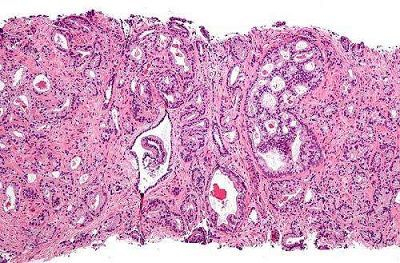

5. Cancer:新技术可帮助鉴定男性前列腺癌相关基因突变

DOI: 10.1002/cncr.30817

尽管前列腺癌是目前困扰男性的最严重的非皮肤性癌症,研究者们对于前列腺癌的遗传背景的了解却十分有限。来自犹他健康大学的研究者们对前列腺癌患者进行了分析,鉴定出了相关的遗传突变特征,这些结果或许能够帮助针对性疗法的改进以及评估患者亲属患前列腺癌的风险。相关结果发表在最近一期的《Cancer》杂志上。

该文章的作者,来自MD安德森癌症中心的Pilié博士希望能够基于前列腺患者的个人临床病史,鉴定出相关的遗传突变。该研究招募了102名被诊断患有前列腺癌的癌症患者,他们同时患有至少一种其它类型的癌症,例如黑色素瘤、胰腺癌、睾丸癌、霍奇金淋巴瘤等等。

利用下一代测序技术,研究者们分析了这群患者生殖系统的相关基因突变的频率。结果显示,有11%的患者在至少一类癌症相关基因中存在突变现象,这表明这一遗传突变或许导致了癌症的发生。此外,通过对患者的个人以及家族病史进行分析,发现其中大部分患者(64%)并不满足遗传检测的标准。这一发现表明,目前的遗传检测手段并不能够有效地检测出携带生殖细胞基因突变的前列腺癌患者的具体情况。

"这篇文章首次描述了通过分析多种癌症(包括前列腺癌)的临床病史从而鉴定患者是否携带生殖细胞基因突变的方法"。事实上,大部分有害的基因突变都与DNA的损伤修复有关,"这些基因的突变会阻碍DNA的自我修复,从而导致癌症的发生"。Cooney说道。

"这一研究能够帮助我们鉴定出具有患前列腺癌高风险的人群,从而指导其尽早地接受诊断与治疗"。